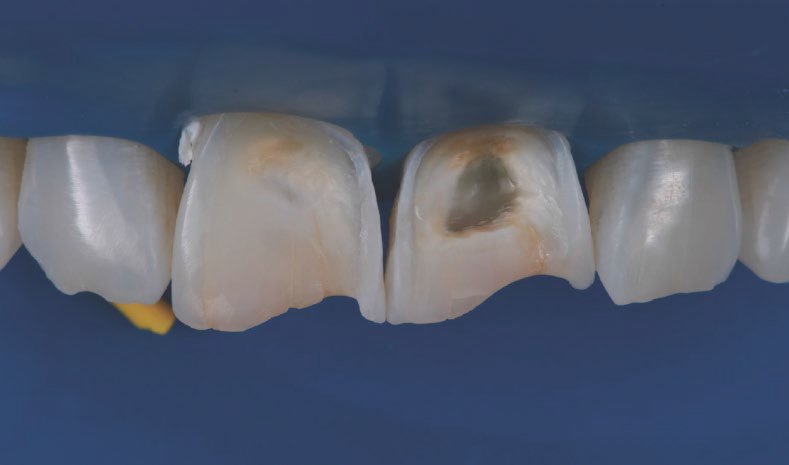

The tooth was prepared under rubber dam using 3M™ Sof-Lex™ Extra Thin Finishing and Polishing edges Disc (coarse). Bevels were created, edges were rounded and the surface was roughened.

The preparation procedure resulted in a round form and a micro-retentive surface structure.

The preparation procedure resulted in a round form and a micro-retentive surface structure

Lateral view of the prepared teeth.